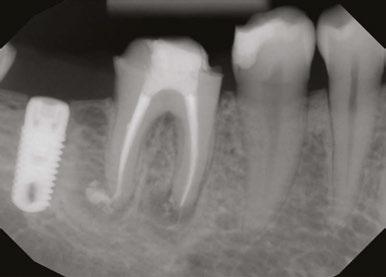

Figure 7: Planned-for access with the scan info on this extremely calcified canine Figures 8 and 9: 8. Deep distal split with PARL. 9. Missed buccal canal; history of previous RCT, post, crown and apico Figure 10: Retreatment consultation. PA from GD Figure 11: Scan images show a previously existing strip perforation

what the literature suggests. And, when I know how many and where the canals are (Figure 13), I can take measurements on the scan and work more efficiently — measuring my working lengths of each canal, appreciating severe curves or calcifications, and knowing where canals can be expected to be located, again, rather than removing unnecessary tooth structure to find if it is there, or not!

As an endodontist, I often treat heavily restored teeth. I am often planning my accesses based on the scan’s information. This saves time and conserves more tooth structure. I’m not looking for canals that may or may not be there, and I’m looking for canals under the targeted/planned access — with the scan, I have an actual map (Figure 7)! CBCT directs me where to go and where to end. It reveals anomalies, which are more common than we think, so I can avoid iatrogenic incidents and provide less invasive treatments. Lower second molars with only two canals occur — often!

I’m also changing my treatment plans based on the data from my CBCT. Sometimes I look at a root canal treated PA and presume I know what I will do: a retreatment or an apico. Another recent, poignant case: a lower incisor with a previous RCT and a previous apico (Figure 9). Usually, once a tooth has had an apico, there may not be much left to offer and most of the time, the default is another apico, especially as there was very little room for an implant on the lower anteriors. I scanned the tooth and saw that a whole canal had been missed — twice! The RCT and the apico had left the buccal canal completely untouched. I changed my treatment plan based on this information!